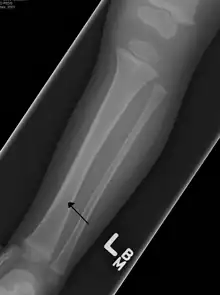

| A toddler's fracture | |

Toddler's fractures are bone fractures of the distal (lower) part of the shin bone (tibia) in toddlers (aged 9 months-3 years) and other young children (less than 8 years).[1] The fracture is found in the distal two thirds of the tibia in 95% of cases,[1] is undisplaced and has a spiral pattern. It occurs after low-energy trauma, sometimes with a rotational component.

Typical symptoms include pain, refusing to walk or bear weight and limping -bruising and deformity are absent. On clinical examination, there can be warmth and swelling over the fracture area, as well as pain on bending the foot upwards (dorsiflexion). The initial radiographical images may be inconspicuous (a faint oblique line) and often even completely normal.[3] After 1–2 weeks however, callus formation develops. The condition can be mistaken for osteomyelitis, transient synovitis or even child abuse. Contrary to CAST fractures, non-accidental injury typically affect the upper two-thirds or midshaft of the tibia.